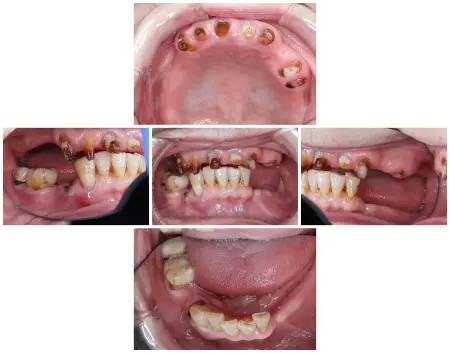

拝見したところ、上下ともに取り外し式の部分入れ歯が装着されていましたが、下顎には状態が悪く温存できない歯が3本あり、噛み合わせの高さがずれる「フレアアウト」も見られました。

フレアアウトは、歯ぐきや歯を支える骨が細菌感染する「歯周病」をはじめとするいくつかの原因が重なって歯並びや噛み合わせが崩れることで生じ、出っ歯やすきっ歯など噛み合わせが悪くなるリスクがあります。

患者様の場合もフレアアウトを放置した結果、上顎のフルジルコニアブリッジが前方に突出し、上下の部分入れ歯も外れやすくなり、しっかり噛むことが難しくなったと考えられました。

このまま治療せずにいると、さらに歯並びと噛み合わせが悪化し、肩こりや頭痛などの症状が生じて全身の健康に悪影響を及ぼす可能性があります。

再び食べ物をしっかり噛めるようにするには、崩れた歯並びや噛み合わせを整える治療と、外れやすい上下の入れ歯も作り直す必要があると診断しました。

また下顎は温存できない歯3本を抜いてから、部分入れ歯を新しく作製します。

まず上下顎の歯を抜き、歯ぐきの回復を待ってから仮の入れ歯を作製しました。